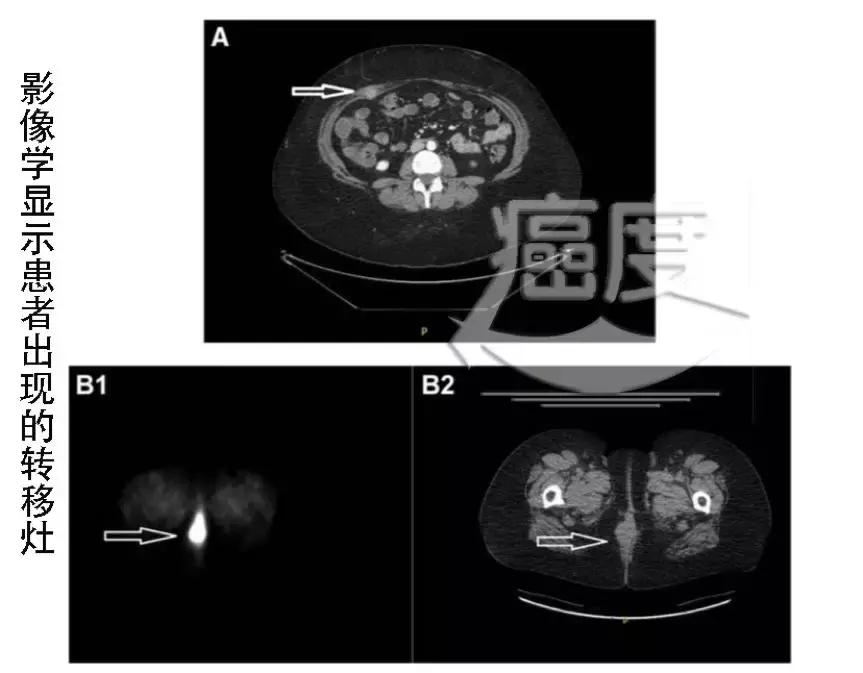

一个月后,影像学显示,患者的右侧腹直肌和脐部出现了转移。使用了激素和他莫昔芬,但没有控制住转移灶的进展。之后对转移灶进行了放疗。

2016年5月,影像学检查发现,会阴部出现了新的转移病灶。之前使用的化疗和放疗未能控制病情的复发。